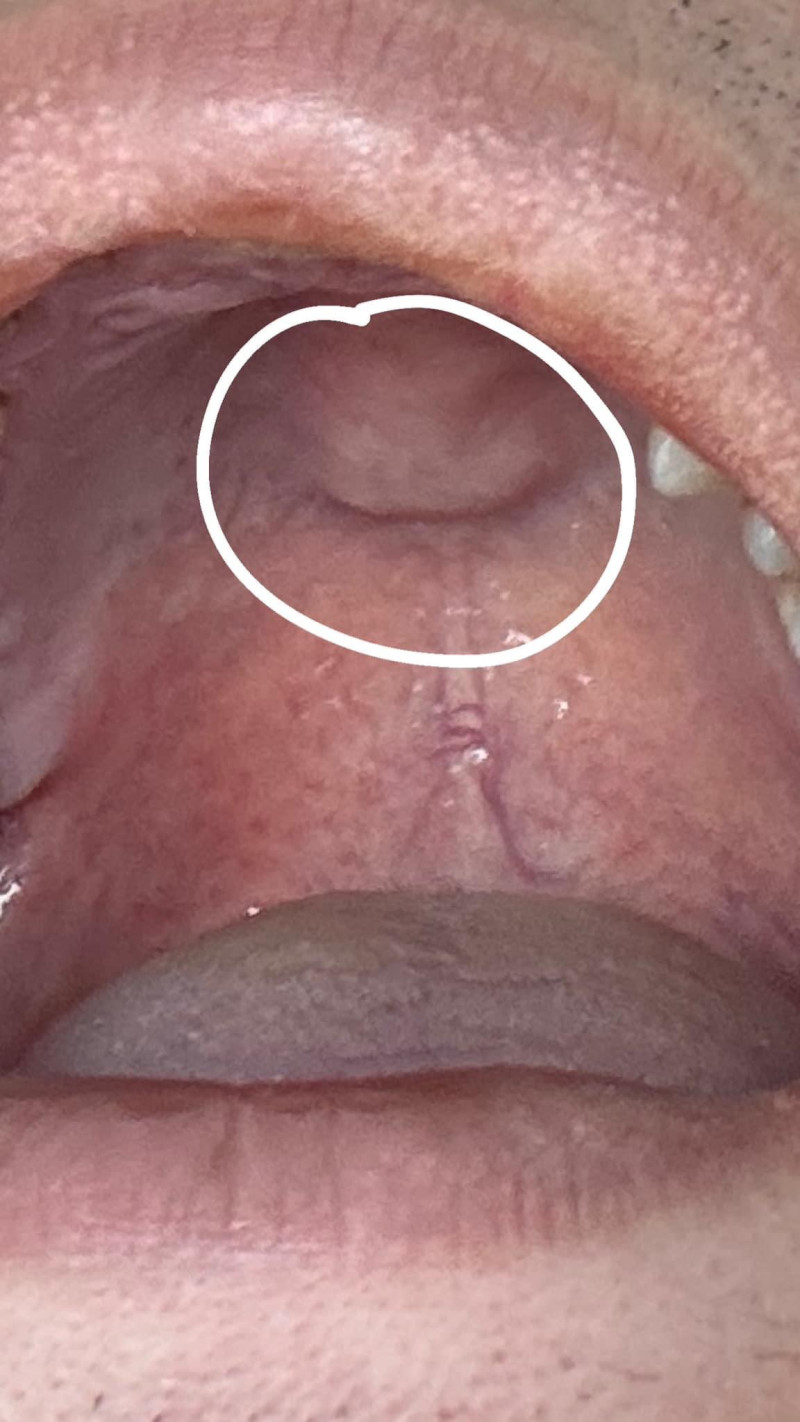

Chào bác sỹ, con em bị sâu răng sưng lệch 1 bên má. 3 ngày nay đã dùng thuốc kháng sinh,chống viêm, Giảm đau nhưng ko đỡ. Bé em trc cũng bị nhưng ko bị lâu và nặng như thế này. Chỗ bị sâu ở răng hàm, bị thủng ở giữa màu nâu,

Em có cho bé đj lấy sâu răng bằng pp dân gian. Nhưng về vẫn chưa đỡ, bs giúp e bh e nên tn ạ. E cũng tính cho con đj khám thì đến đó bs sẽ làm những gì có đau ko ạ